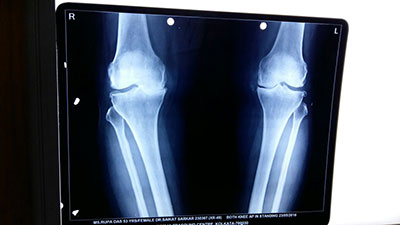

Case 7: Total Knee Replacement

54 years female was suffering from both knee pain for last 4-5 years. She had bilateral advanced osteoarthritis knee.

Patient underwent knee replacement surgery in two stages. 1st right knee was replaced after 8 months left knee was replaced.

X-RAY 1

knee advanced stage of osteoarthritis